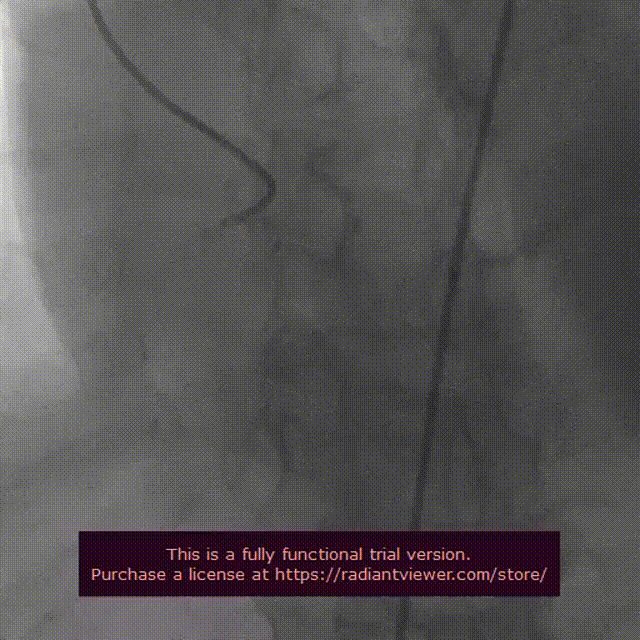

因主动脉弓角度成锐角,使导丝跨瓣异常困难,多次跳出,在同侧端使用snare,在snare辅助下导丝才顺利跨瓣

采用20mm球囊扩张,有轻微腰征,无漏,患者术中几近循环崩溃